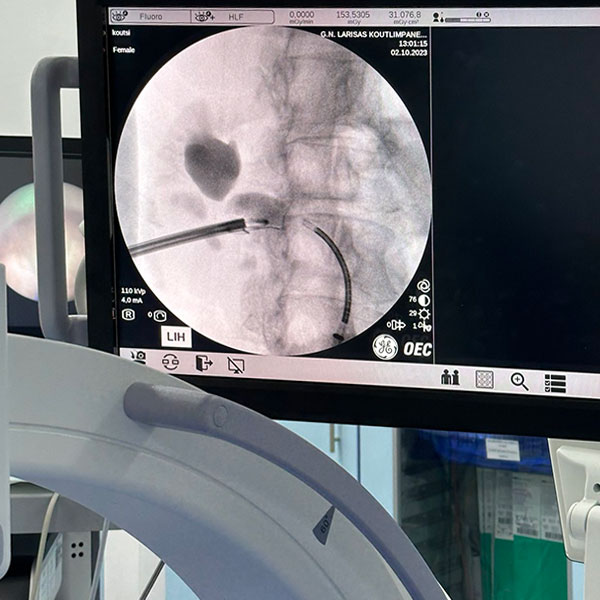

• Εύκαμπτη laser νεφρολιθοτριψία

• Εύκαμπτη laser ουρητηρολιθοτριψία

Επίσης, παρέχει διαδερμική νεφρολιθοτριψία με laser, ουρητηροσκοπική λιθοτριψία με laser, υπερηχοτομογραφικό έλεγχο, εύκαμπτη κυστεοσκόπηση, διορθική βιοψία προστάτη και αναλαμβάνει όλες τις μικροεπεμβάσεις, καθώς επίσης και την αντιμετώπιση της ακράτειας ούρων και τον ουροδυναμικό έλεγχο.